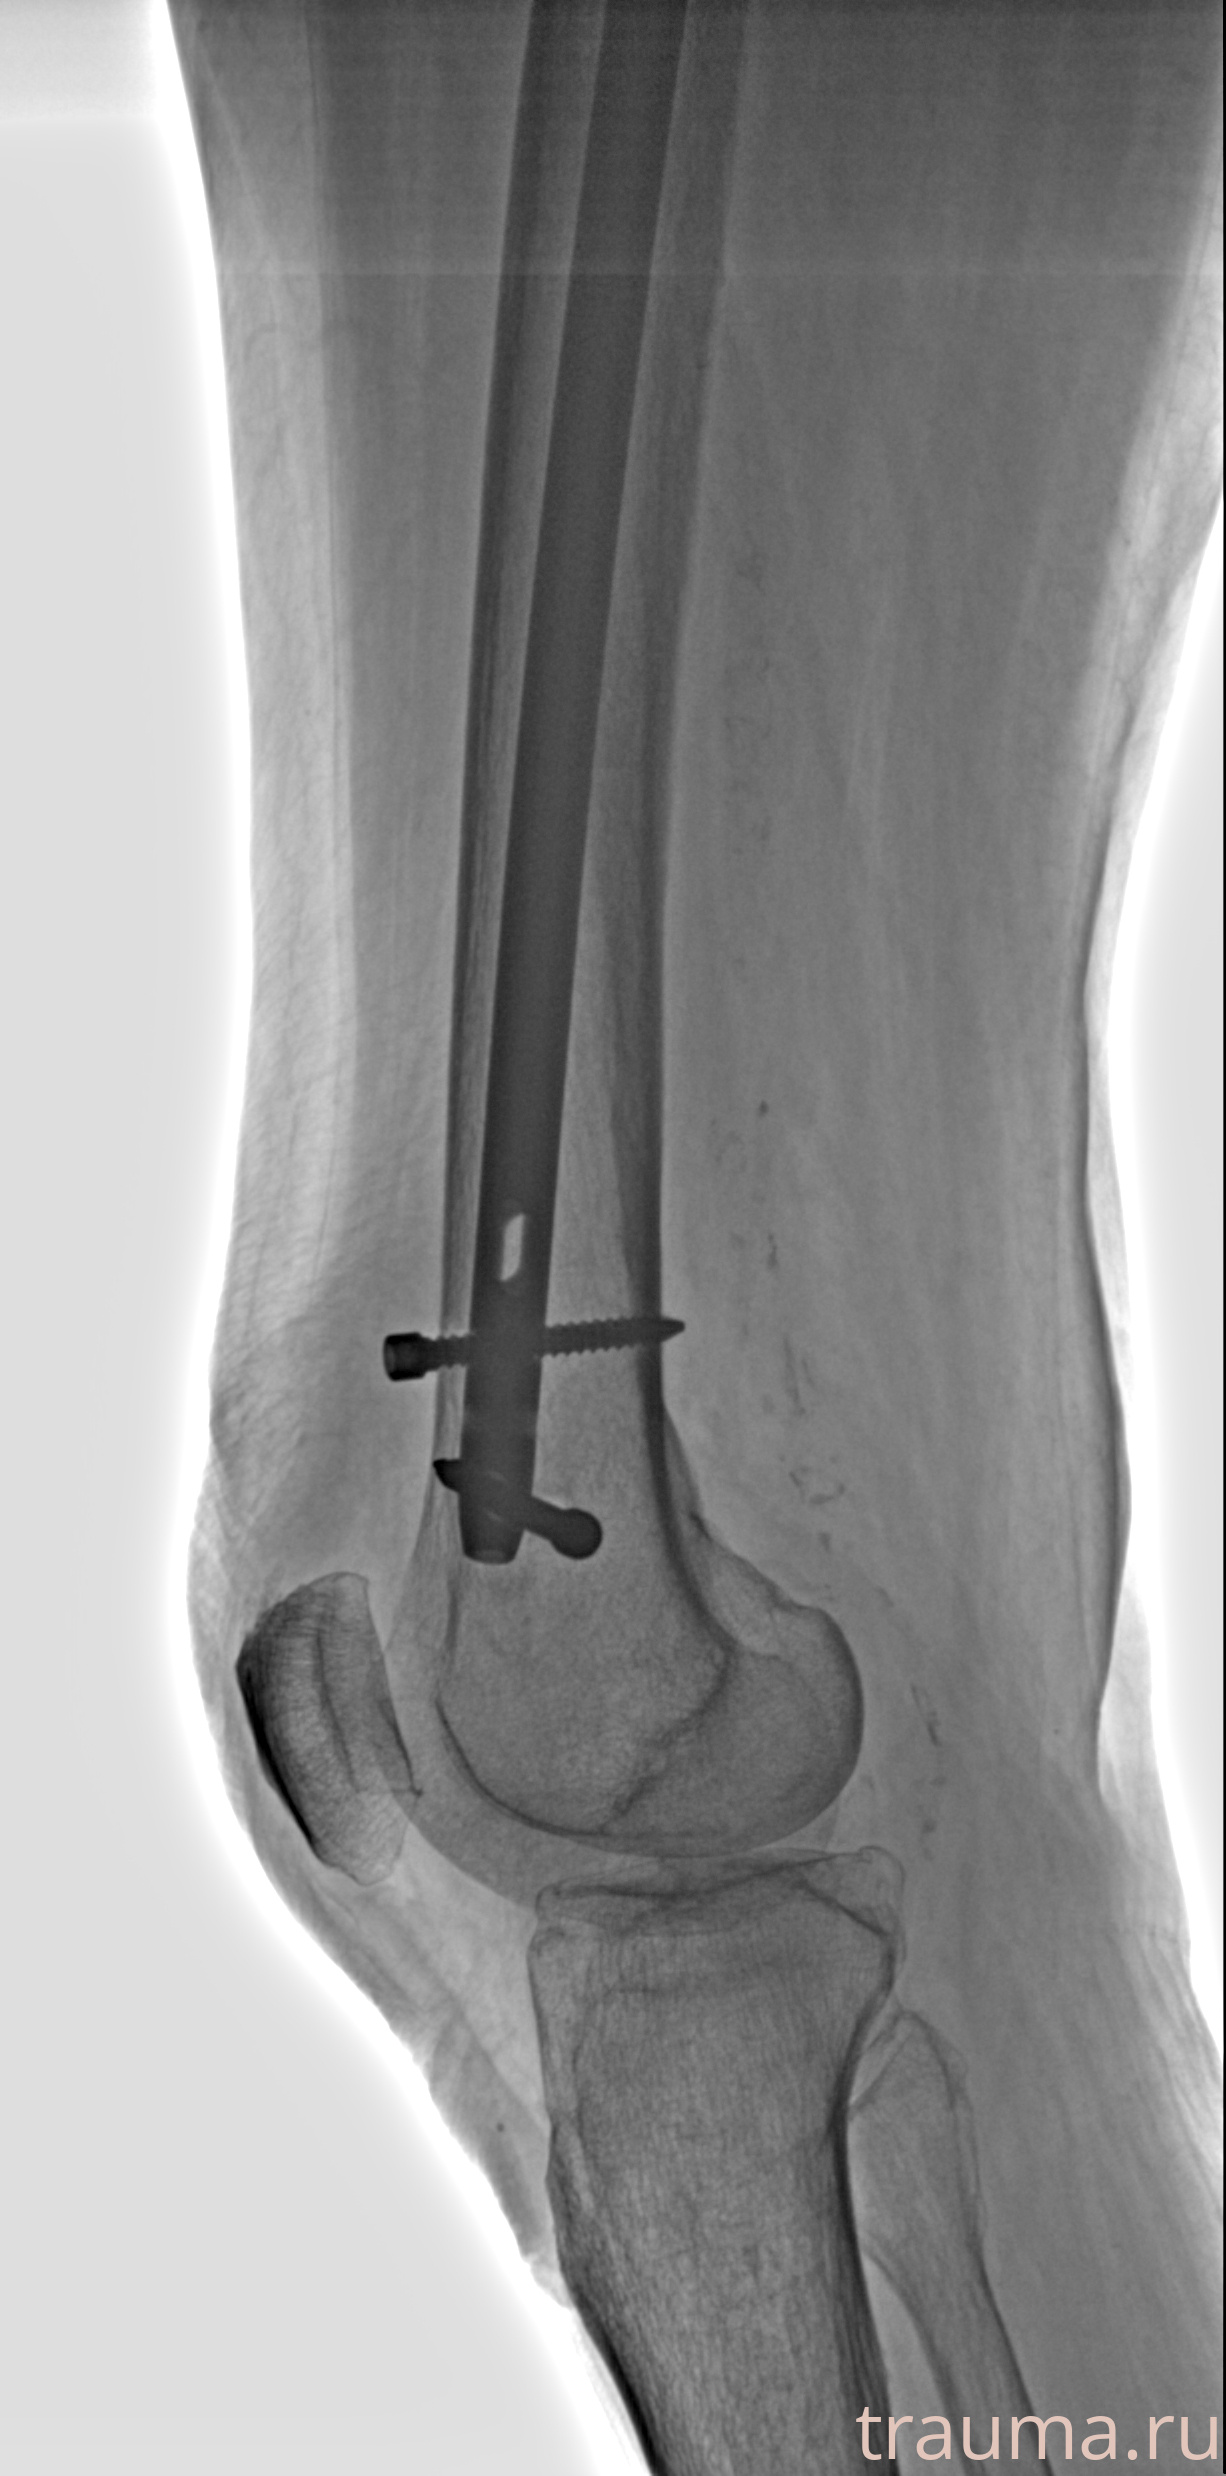

Рентгенограммы

Рентген на дому: по вашему адресу приезжает врач-рентгенолог, травматолог-ортопед с мобильным рентгеновским аппаратом, проводит диагностику травмы или заболевания, делает необходимые рентгенограммы, дает рекомендации по дальнейшему лечению. Получить качественные снимки в домашних условиях возможно благодаря уникальной методике, разработанной МосРентген Центром для института  Склифосовского